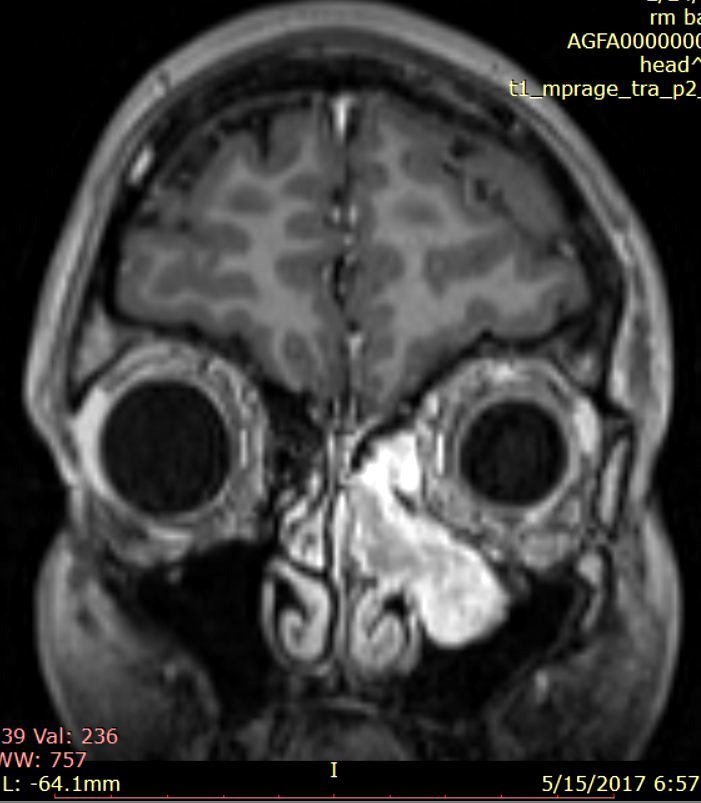

Examenul pentru reevaluare endocrinologică (Doamna Dr. Simona Jercălău – Brain Institute, Spitalul Monza) ridică suspiciunea unei secreţii ectopice paraneoplazice de ADH, contrazicând astfel diagnosticul de SIADH stabilit în urmă cu 5 ani. Coroborarea cu diagnosticul ORL, cu examenele imagistice şi cu literatura de specialitate (20 de cazuri descrise în lume până în anul 2014) stabilesc diagnosticul prezumptiv de estezioneuroblastom etmoidal stâng extins fronto-maxilar secretant de vasopresină (stadializare Kadish – grup b) şi se decide efectuarea intervenţiei chirurgicale endoscopice transnazale în scop diagnostic şi curativ (fig. 2).

Fig.2: Examen RMN craniocerebral cu substanță de contrrast efectuat preoperator